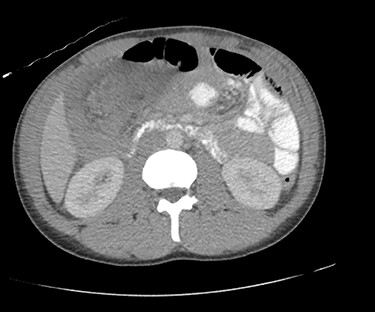

Due to diagnostic uncertainty, the patient underwent a computed tomography (CT) of the abdomen and pelvis with intravenous and oral contrast, which demonstrated ileo-colic intussusception, a distended ileum and no other features of bowel obstruction. Coronal and axial views of the CT scan showing the ileocolic intussusception are displayed in Figs 1 and 2, respectively.

CT of the abdomen and pelvis with axial view showing ileo-colic intussusception.